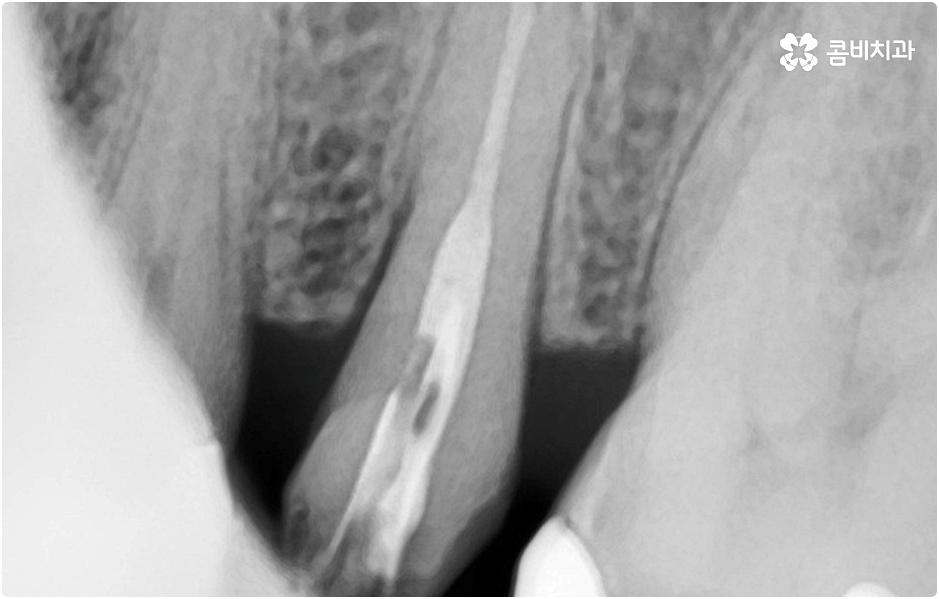

임플란트 시술을 받을 때 치아를 상실한 원인이 무엇인지, 상실하고 나서 그대로 둔 시간이 얼마나 되는지, 현재 치아나 잇몸 등 구강 내부 상황이 어떤지 등등을 먼저 꼼꼼하게 파악할 필요가 있는데요. 예를 들어 20대임플란트 를 받게 된 원인이 사고와 같은 외부 충격으로 인한 것이고 시간이 많이 흐르지 않은데다 다른 구강 질환 (충치나 치주 질환) 이 크게 문제가 되지 않는 상황이라면 젊은 나이이기 때문에 바탕이 되는 잇몸뼈 건강이 비교적 양호할 것이라고 예상할 수 있으며 이런 경우 즉시 임플란트 방식을 검토해 볼 수 있어요. 면밀한 정밀 검사 후 가능하다는 의료진의 진단이 내려진다면 당일에 인공 치근을 심고 임시 크라운까지 올려 바로 사용할 수 있는 즉시 임플란트 방식을 통해 보다 빠르고 간편하게 수복을 할 수 있습니다.

그러나 언급했던 것처럼 잇몸뼈 상태에 대해서 먼저 체크해 봐야 하기 때문에 누구나 받을 수 있는 치료 과정은 아니라는 점을 분명히 알아두실 필요가 있습니다. 이렇게 잇몸뼈를 보충해야 하는 상황 뿐 아니라 충치 또는 치주 질환을 먼저 깨끗하게 치료해야 하는 상황, 상악동까지의 거리가 너무 짧아서 거상술을 통해 혹시 모를 천공과 염증을 방지해야 하는 상황 등 여러 가지 선치료가 필요한 케이스들이 있을 수 있기 때문에 먼저 환자분들의 상황을 자세하게 파악하기 위해서 꼼꼼한 검진을 해 볼 필요가 있으므로 3D CT 등 정밀 검진 장비 보유 여부가 필수적이라고 말씀드린 거예요.

그러나 치아가 빠진 후부터 잇몸뼈는 수축을 하기 시작하기 때문에 오랜 기간 그대로 방치를 하게 되면 잇몸이 내려앉아 주변 치아가 쓰러지고 치열이 흩뜨러지며 악관절까지 좋지 않은 영향을 받게 되는 등 구강 내부적으로 문제가 더 커질 수 있으며, 치아가 크게 부러진 뒤 치근이 일부 남아 있는 상황이라고 하더라도 기능을 전혀 하지 못하여 주변 치아와 잇몸에 지속적인 부담을 주고 있거나 해당 부위를 통해 감염이 일어날 가능성이 높다면 이를 발치하고 빠르게 기능적 심미적 대체를 해 줄 필요가 있으니 될 수 있는대로 바로 치과로 내원하셔서 검진부터 꼼꼼하게 받아보시고 그에 적합한 치료를 받으시길 권유드리고 있어요.